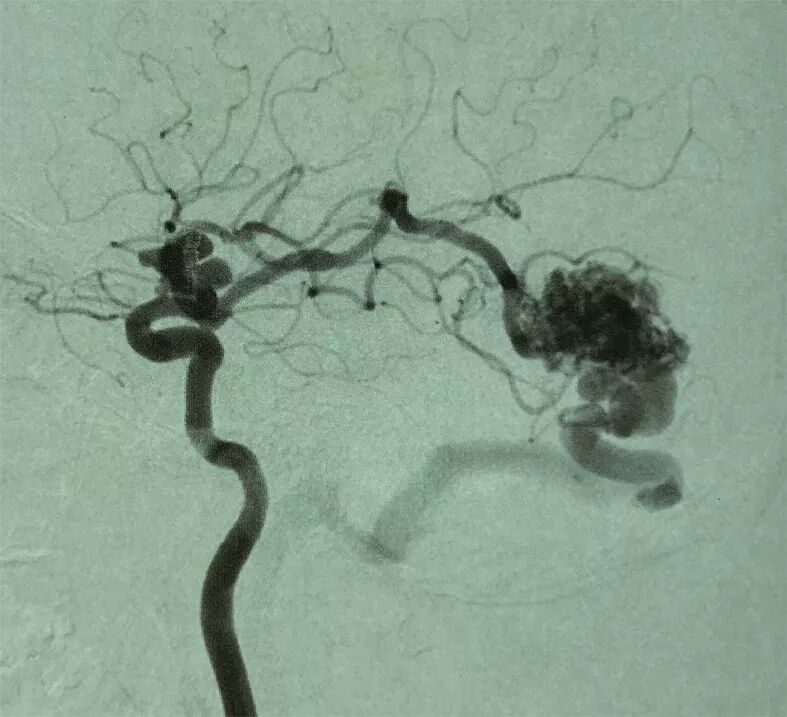

2. 术前DSA示:右侧大脑中动脉主供血AVM,向横窦乙状窦引流,合并多发血流相关性动脉瘤。

AVM合并动脉瘤临床上常有碰到,发生率文献报道10-20%不等。治疗方法上主要有显微手术切除和血管内介入治疗。本例为右侧大脑中动脉供血的血管畸形伴发有多个血流相关动脉瘤进行显微手术一期处理多个病变的病例。

AVM合并动脉瘤临床上常采用Redekop方法分为3型:Ⅰ型动脉瘤在AVM内部,为AVM团内型;Ⅱ型为血流相关型,又分为两型:Ⅱa:动脉瘤在AVM主要供血动脉主干的近端,Ⅱb-动脉瘤在AVM供血动脉远端。Ⅲ型动脉瘤与AVM无关。IIa型动脉瘤多需要处理,IIb型动脉瘤位于供血动脉远端,在切除或栓塞AVM后常会消失,一般采用先动态观察,根据发展情况,采取适当的处理策略。

本文报道病例未破裂的AVM合并供血动脉血流相关性动脉瘤,按Redekop分类,本例患者AVM同时伴发供血动脉近端(IIa)及供血动脉远端(IIb)动脉瘤。我们首选在电生理监测下,控制AVM供血的大脑中动脉,采用无出血手术操作技术,沿AVM和周边脑组织分界的胶质增生带分离完整切除AVM。对于伴发的供血动脉血流相关性IIa和IIb动脉瘤采用不同的策略。近端IIa动脉瘤一期显微夹闭处理,远端IIb动脉瘤随访观察的处理策略。手术顺利,术后病人恢复良好,没有功能障碍。